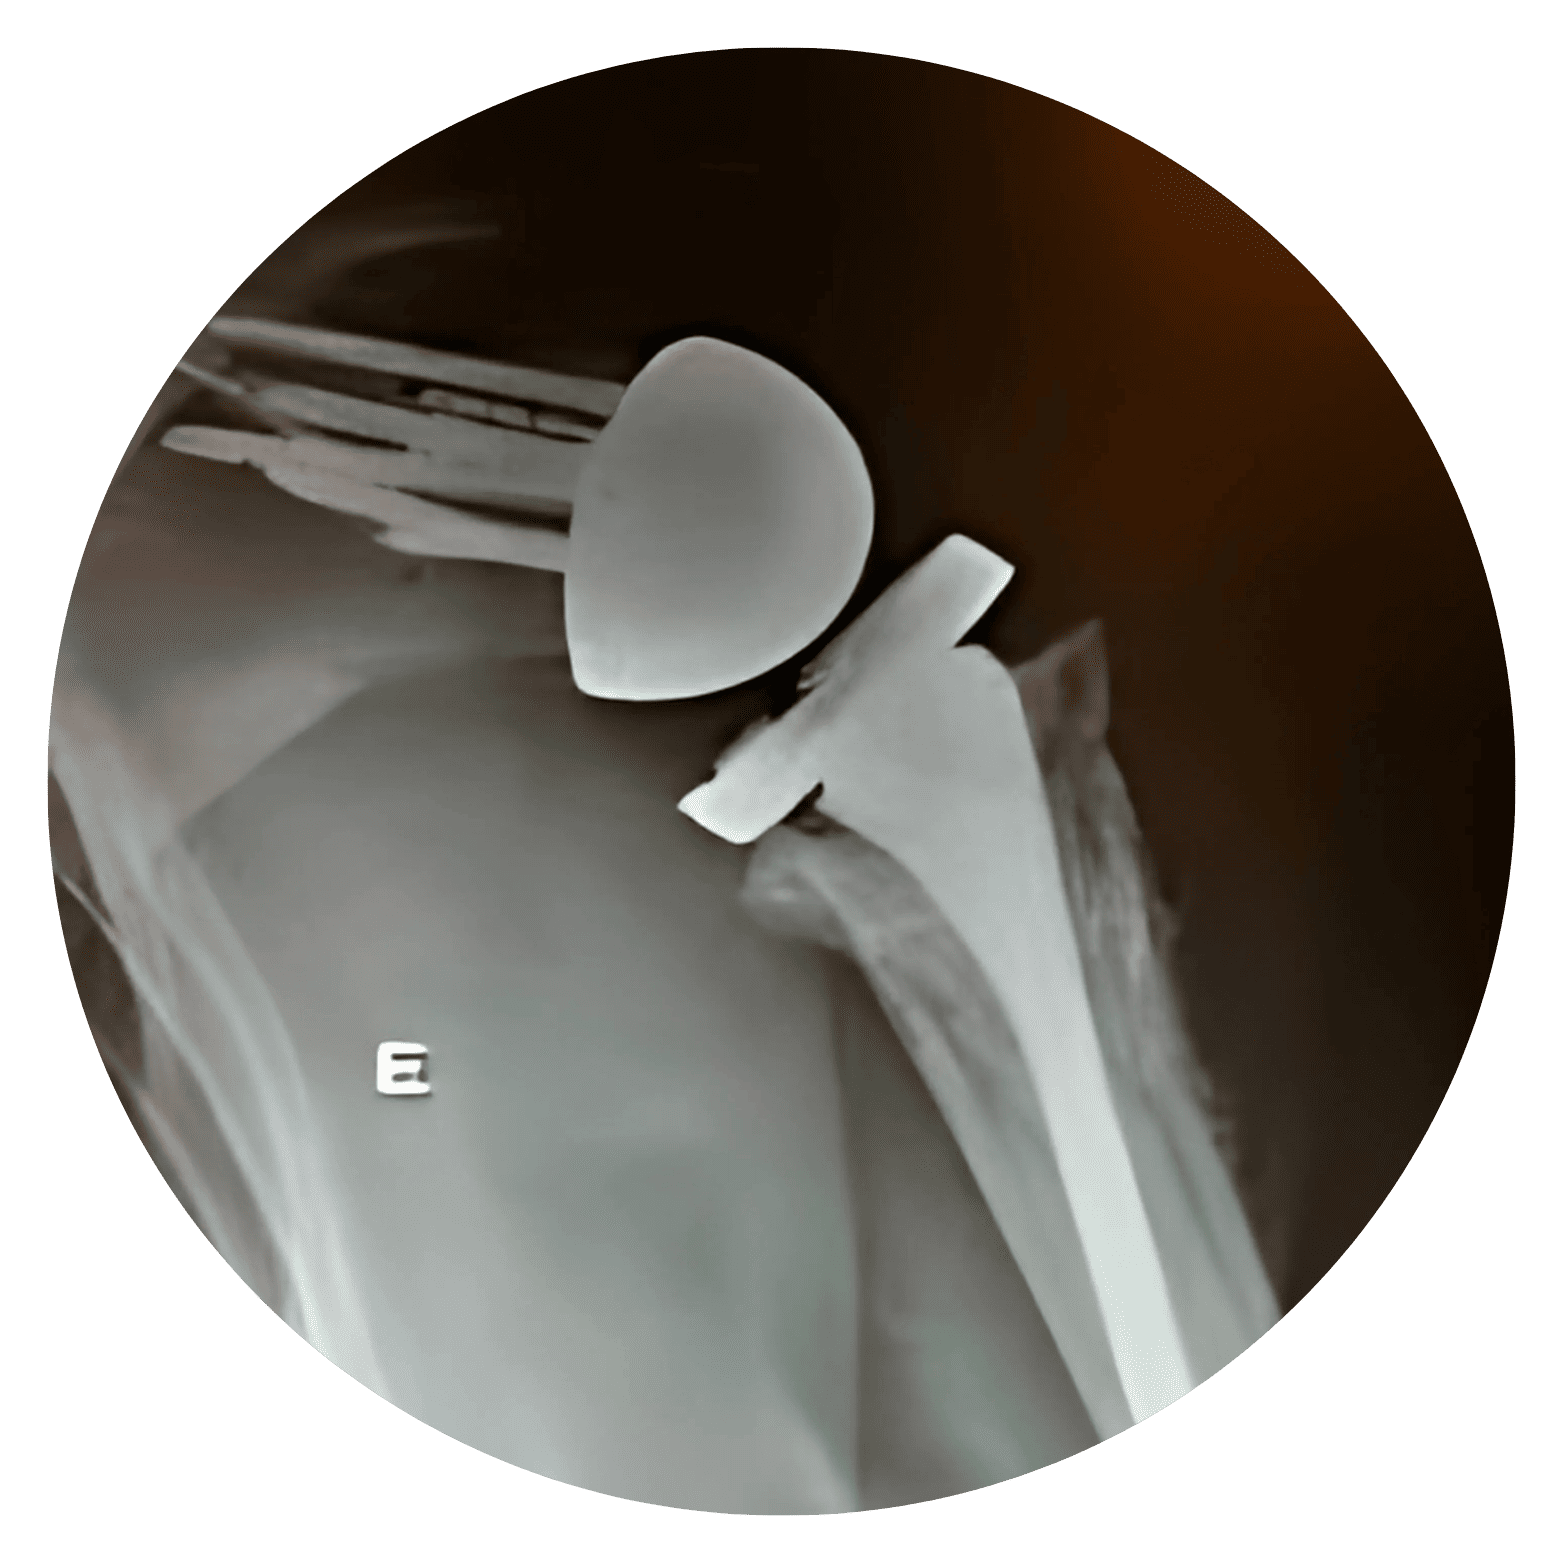

Lesão do Manguito Rotador Sentir uma dor persistente no ombro ao tentar pegar um objeto em uma prateleira alta, ter dificuldade para vestir uma jaqueta